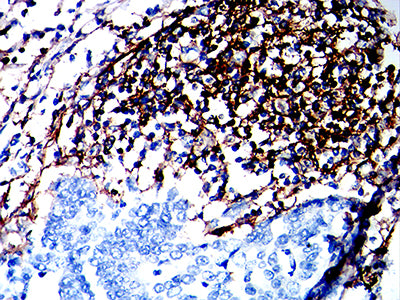

TD-323184.jpg

Immunohistochemical analysis of paraffin-embedded human gastric cancer tissues using CD180 mouse mAb with DAB staining.